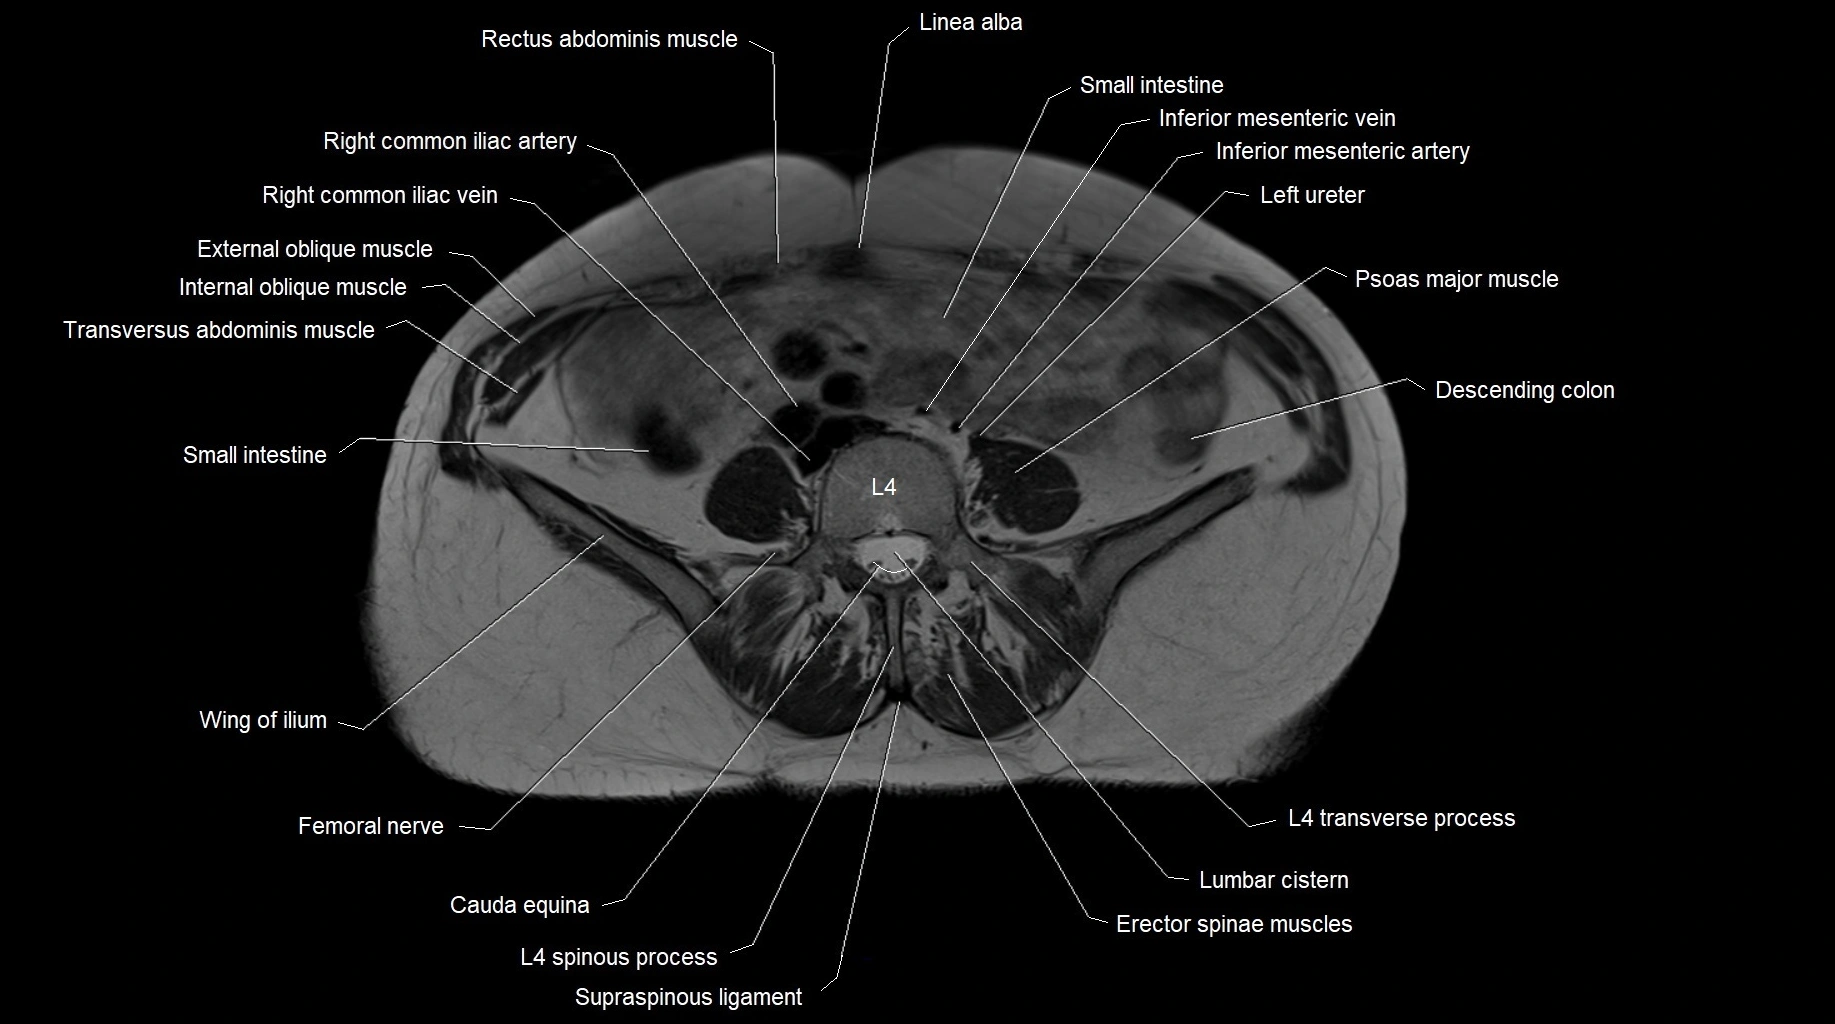

- Erector spinae muscles

- Inferior mesenteric artery (IMA)

- Inferior mesenteric vein

- Linea alba

- Psoas major muscle

- Quadratus lumborum muscle

- Transverse abdominal muscle